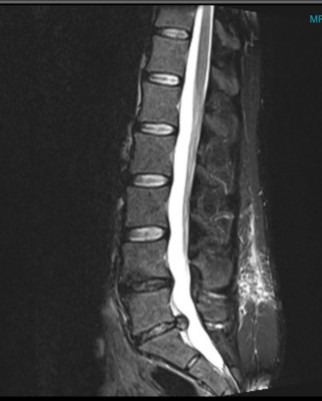

Hi my name is Mike, my best friend Carly who is 31 needs artificial disc replacement surgery for 2 discs. First is the disc between L4/L5, the second is between L5/S1. She has had back pain for quite a few years and in April 2025 her disc between L5/S1 herniated so bad that it took walking and she went in for a discectomy in August 2025 and afterwards had hope of no pain but a week and a half later the same disc re-herniated.

We went in for a special consultation with German neuro surgeons who agreed that the two disc's needed replacing. they were both very honest and knowledgeable and assured us that they're is a very, very high success rate. we also got to talk to a few people that have had the surgery and they have had great lives after having disc's replaced. The surgery is very expensive and is not available in Canada as they won't approve the artificial disc's for the replacement surgery, so she needs to travel to Germany to get the best care and latest technology to have it done properly. Any help you would be willing to offer would be greatly appreciated in the hopes that she will finally be able to have a happy and pain free life to enjoy.